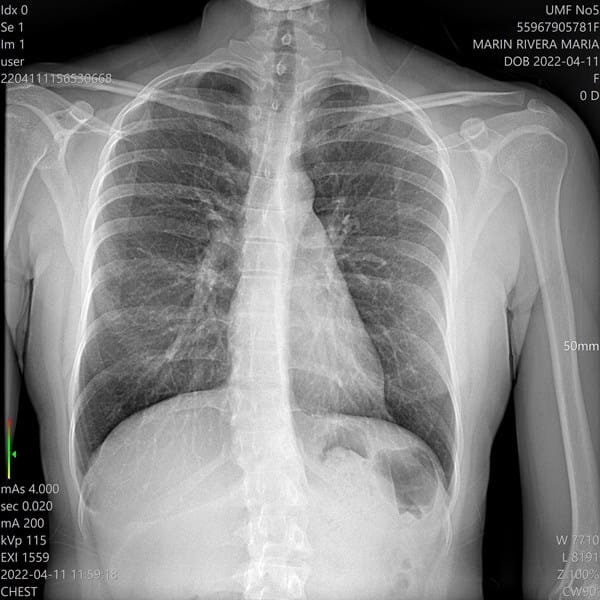

Hola esta es otra radiografía tengo 20 años he estado haciendo ejercicios para la escoliosis, pero no se si con los ejercicios mejore por favor usted viendo más o menos la radiografía cree que sea moderada o leve

I. Hola Compañera, le agradezco el voto de confianza pero por desgracia no tengo ninguna formación para poder opinar a ese nivel -ni a ninguno en realidad-, pero mi punto de vista personal, aunque sea desde la ignorancia, es que su escoliosis es moderada, no leve.

Sin embargo, según estoy leyendo y viendo, estaría equivocado, su escoliosis se enmarca más bien en un nivel leve, o a lo sumo intermedio entre leve y moderada,

El tipo de escoliosis que padece, pienso sería de clase torácico-lumbar, (más bien torácica según este esquema) dado que, simplificando mucho, existen hasta cuatro tipos de esta,